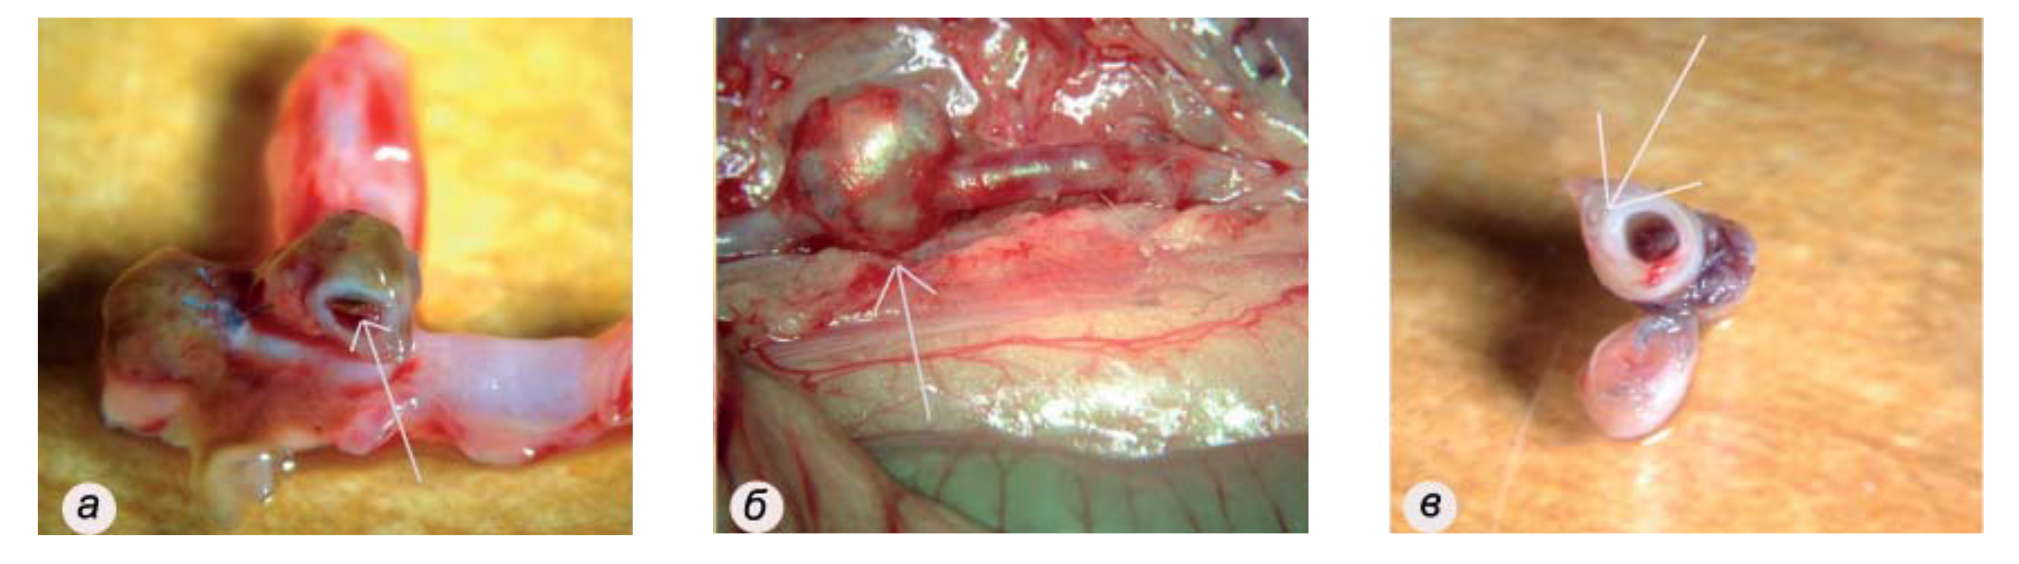

Интима протеза гладкая, блестящая, неотличима от интимы собственной аорты реципиента (рис. 5), признаков инфекционно-воспалительных изменений нет. В группе ДА гибели животных в установленный период наблюдения не было. Однако только у 4 из 10 животных отсутствовали видимые морфофункциональныеизменения. У остальных 6 крыс наблюдали развитие патологий, в дальнейшем, несомненно, вызвавших бы гибель: тромбоза (n=2, рис. 6а), аневризмы протеза (n=2, рис. 6б) и гиперплазии интимы со стенозом просвета до 50% (n=2, рис. 6в).

Рис. 6. Патологии, развивающиеся в течение 1 мес после трансплантации децеллюляризированной аорты: тромбоз (а), аневризма (б), стеноз (в)